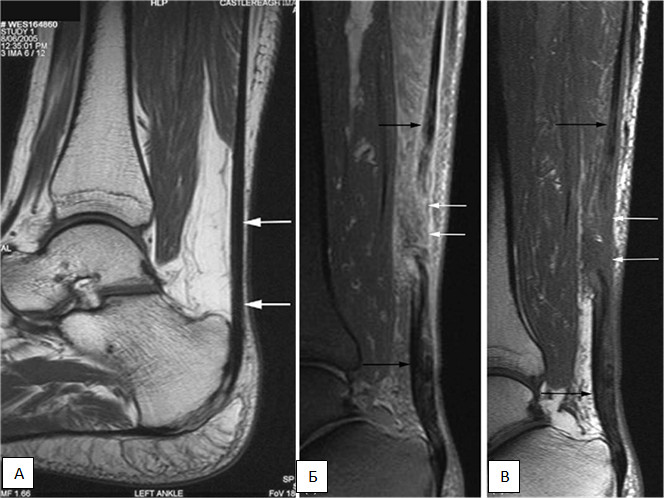

При разрыве ахиллова сухожилия применяется клинический метод для установления диагноза. Врач собирает анамнез, проводит визуальный осмотр поврежденной области и пальпирует участок, где, вероятно, произошел разрыв. Обычно этих действий достаточно для определения нарушения целостности ахиллова сухожилия. Дополнительные диагностические процедуры могут включать УЗИ и МРТ.